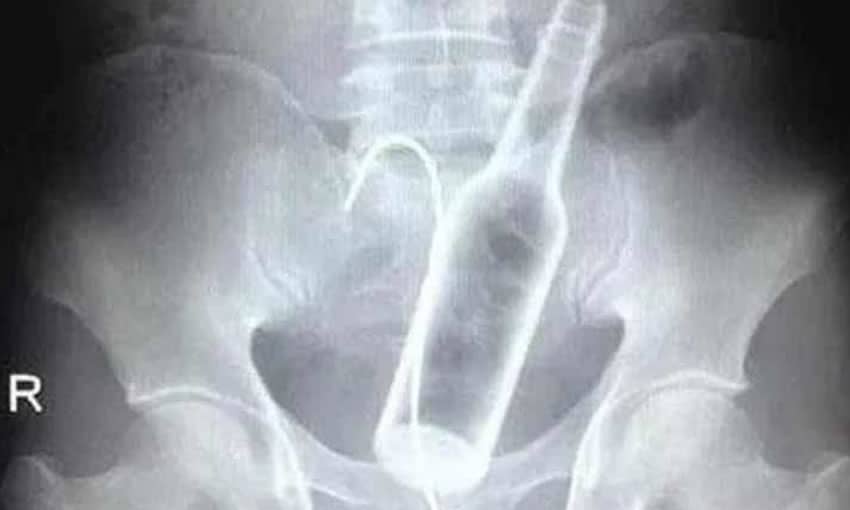

Um homem deu entrada na Santa Casa de Poços de Caldas na madrugada da última segunda-feira, 29, após inserir duas garrafas na região retal, sendo